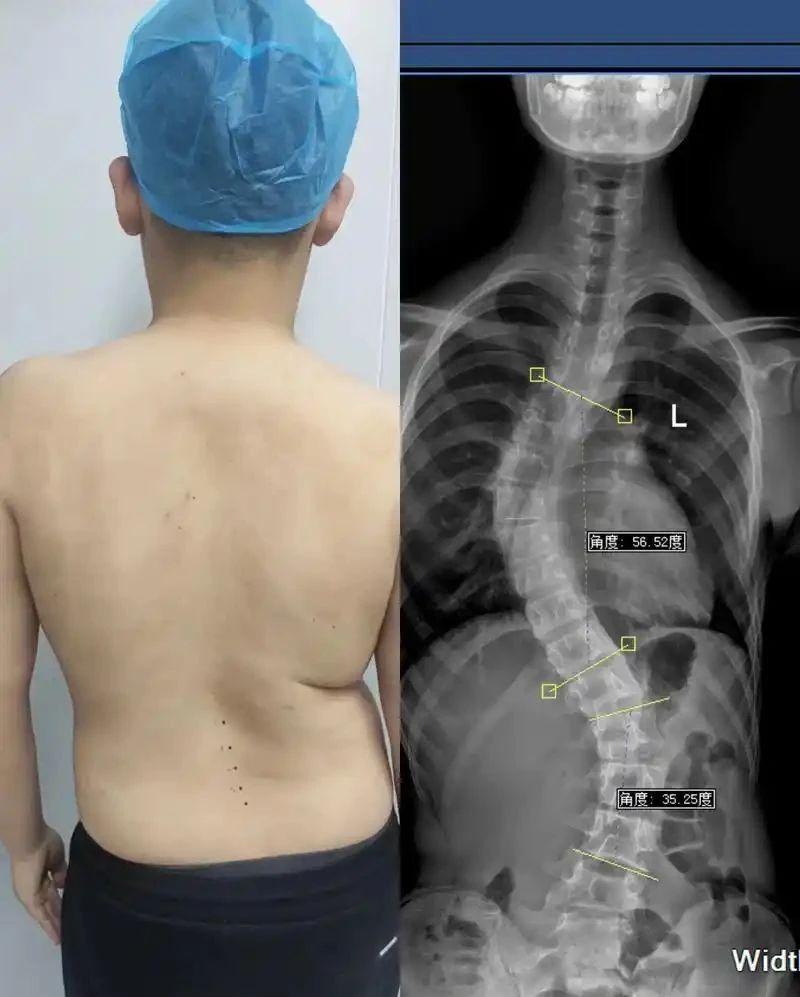

近些年,脊柱问题越来越严重,甚至越来越年轻化!

脊柱侧弯、脊柱炎、颈椎病、腰椎间盘突出...

这些病单看名字其实还好,很多都是“常见病”,但这些病一旦得了一种,时间久了对我们的身体都是“毁灭性”的打击!

现如今,有脊柱问题的人越来越多,脊柱病也越来越年轻化,而究其病因,很多都适合我们不良的生活习惯有关!

二郎腿、“葛优瘫”、躺着看手机、久坐、缺少运动...

这些都是引起脊柱问题的“直接原因”,所以越是患者与日俱增的今天,掌握“长远脊柱自然疗法”就越有必要性!